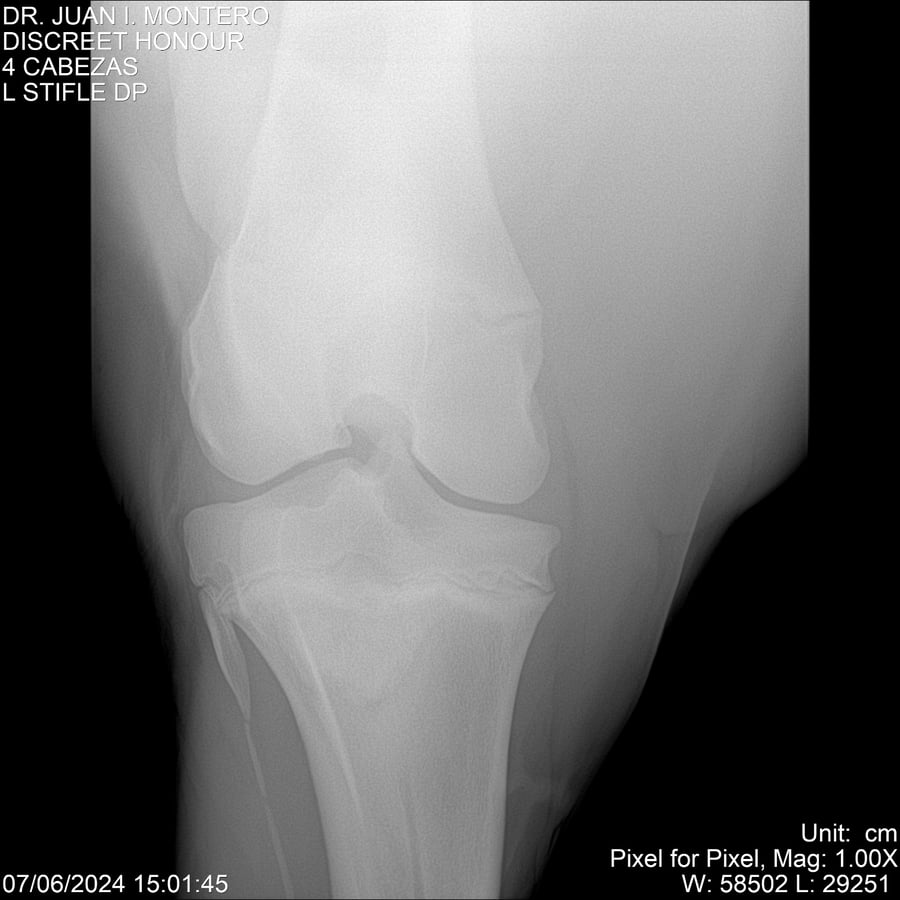

LOTE 6, DISCREET HONOUR 🔥 🔥 🔥 Lote Anterior Volver al remate Lote Siguiente Ficha Contacto Montevideo - Ficha del Lote Identificador: #281093 Categoría: Yeguarizos Montevideo - 82 Visualizaciones ClicData Contacto Empresa: Abelenda N. R., Walter Hugo Nombre*: Teléfono* : E-mail* : Mensaje Enviar Registrese gratis Este contenido Exclusivo está disponible sólo para usuarios registrados Ingresar